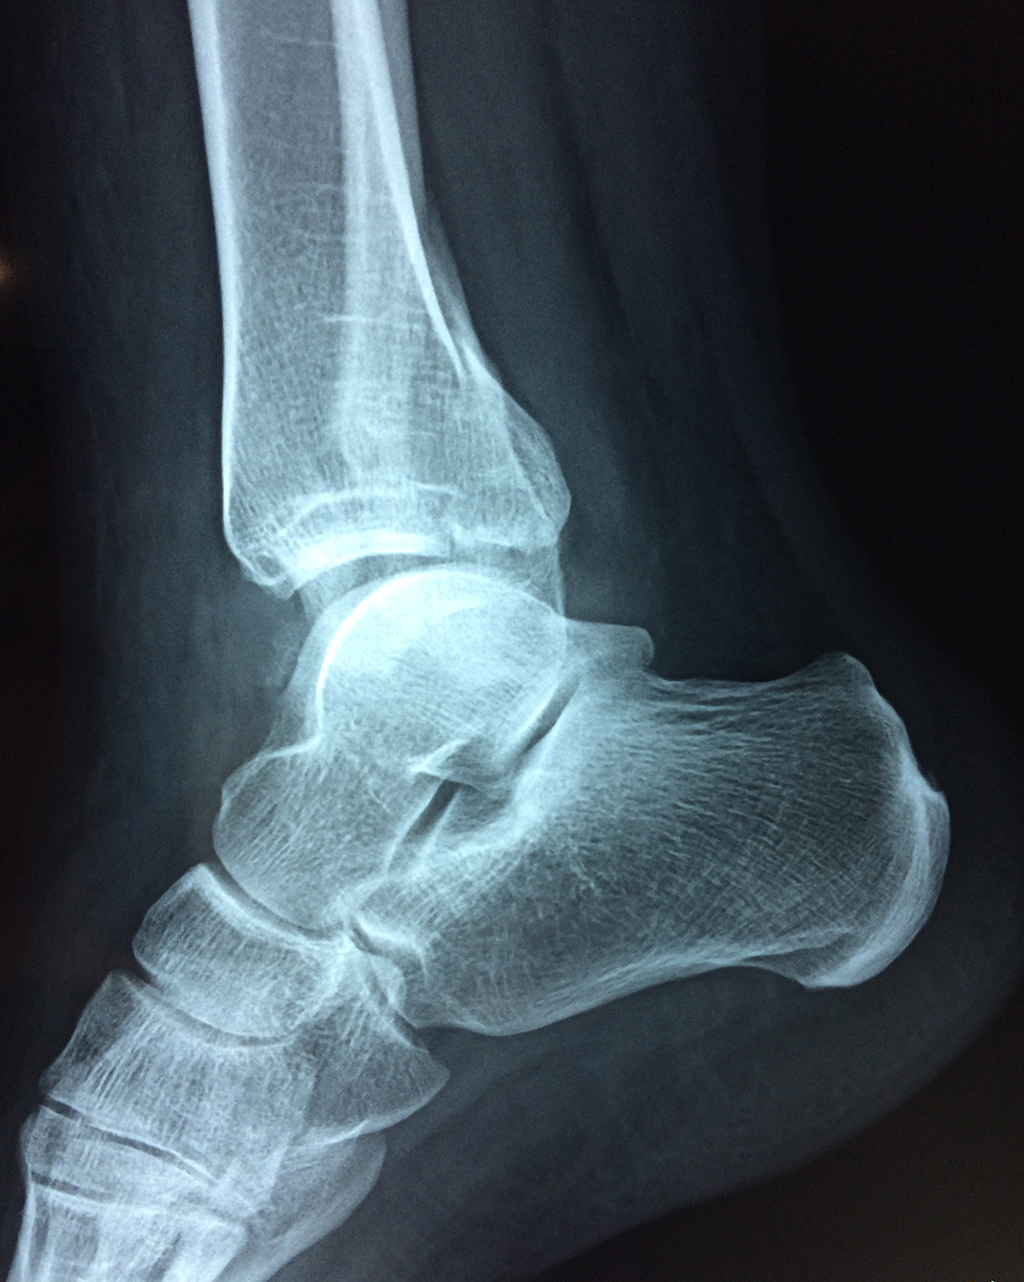

Una fractura de tobillo es la rotura de uno o más de los huesos del tobillo. Estas fracturas pueden ser:

Cuando se necesita cirugía, es probable que esta implique el uso de clavijas de metal, tornillos o placas para sostener los huesos en su lugar mientras la fractura se consolida. Los elementos de soporte pueden ser temporales o permanentes.